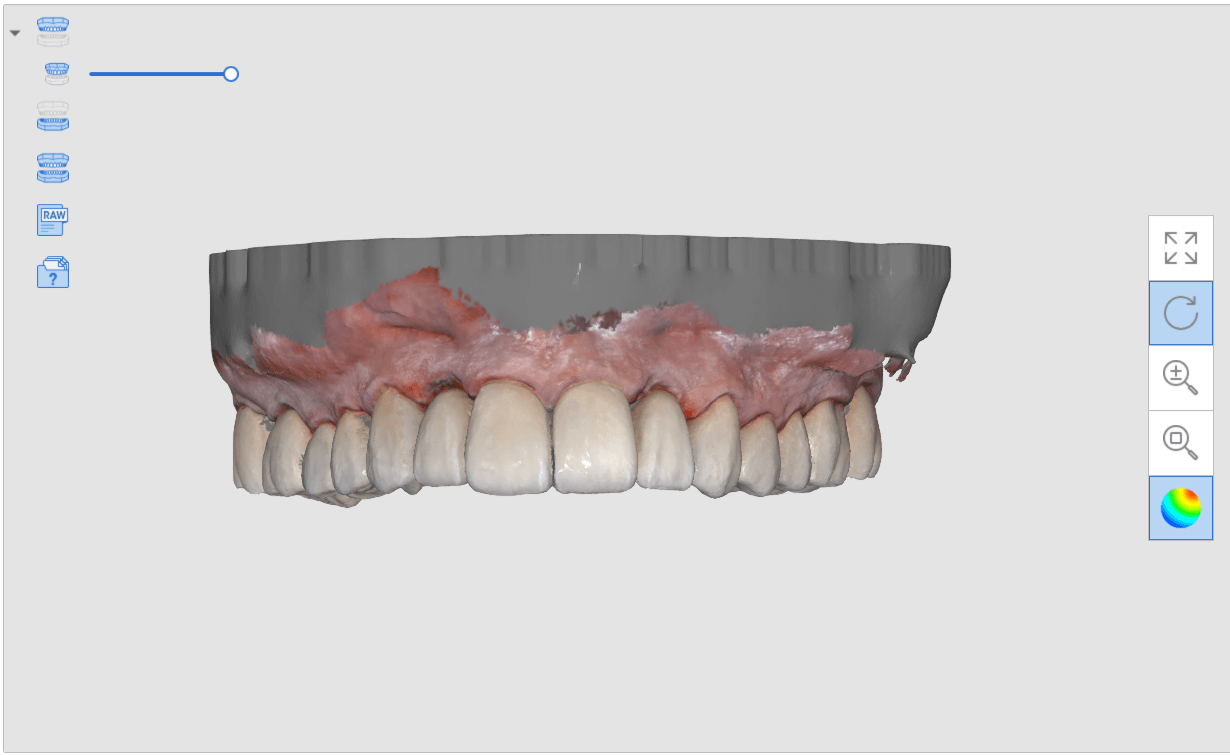

Anterior preps scanned along with the opposing and the initial bite

segmental imaging to building a master model

upper and lower models related to each other for design

Post op intra-oral scan with Medit i500 to capture irritated and hemorrhaging tissue (for demonstration purposes only)